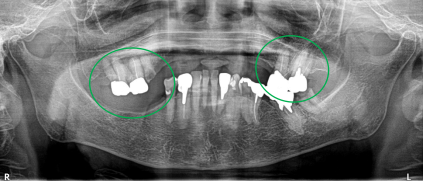

Before

緑丸は、上顎5本残っている歯